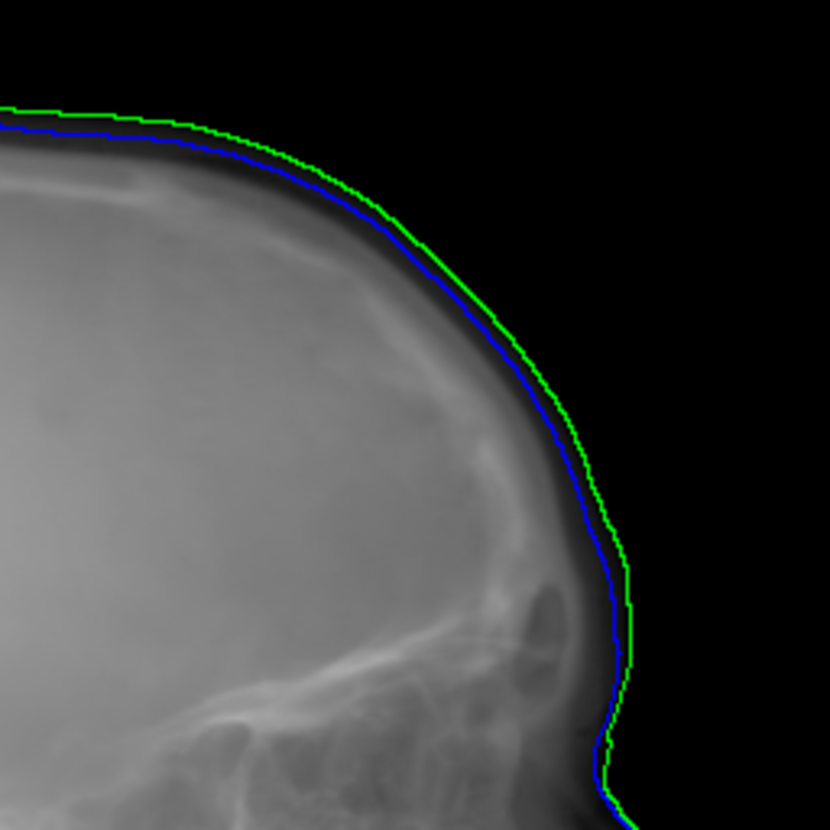

Refer to caption

(a) Real cephalogram

(b) Synthetic cephalogram

(c) Plot of samples and sigmoid curves

Fig. 2: Image contrast difference between real conventional cephalograms and RayCast synthetic cephalograms: (a) a real cephalogram example; (b) a RayCast synthetic cephalogram example; (c) the plot of samples between RayCast synthetic cephalograms and real cephalograms with an original sigmoid curve (red) and our proposed modified sigmoid curve (blue).

In Fig. 2, one real conventional cephalogram example and one example of 𝒈𝒈\boldsymbol{g} are displayed, where evident image contrast difference between these two images is observed. It is because the X-ray films used in conventional cephalograms have the special nonlinear optical property that the characteristic curve between optical density and logarithmized X-ray exposure has a sigmoid-like shape [42]. According to the Lambert-Beer law, the logarithmized X-ray exposure is equivalent to the attenuation integral. It indicates that the intensity relation between the desired cephalogram and the attenuation integral image 𝒈𝒈\boldsymbol{g} should also exhibit a sigmoid-like curve. Therefore, to make the image contrast of synthetic cephalograms similar to conventional cephalograms, a sigmoid intensity transform is necessary.

where the intensity transform is a modified sigmoid function, illustrated as the blue-dotted curve in Fig. 2.